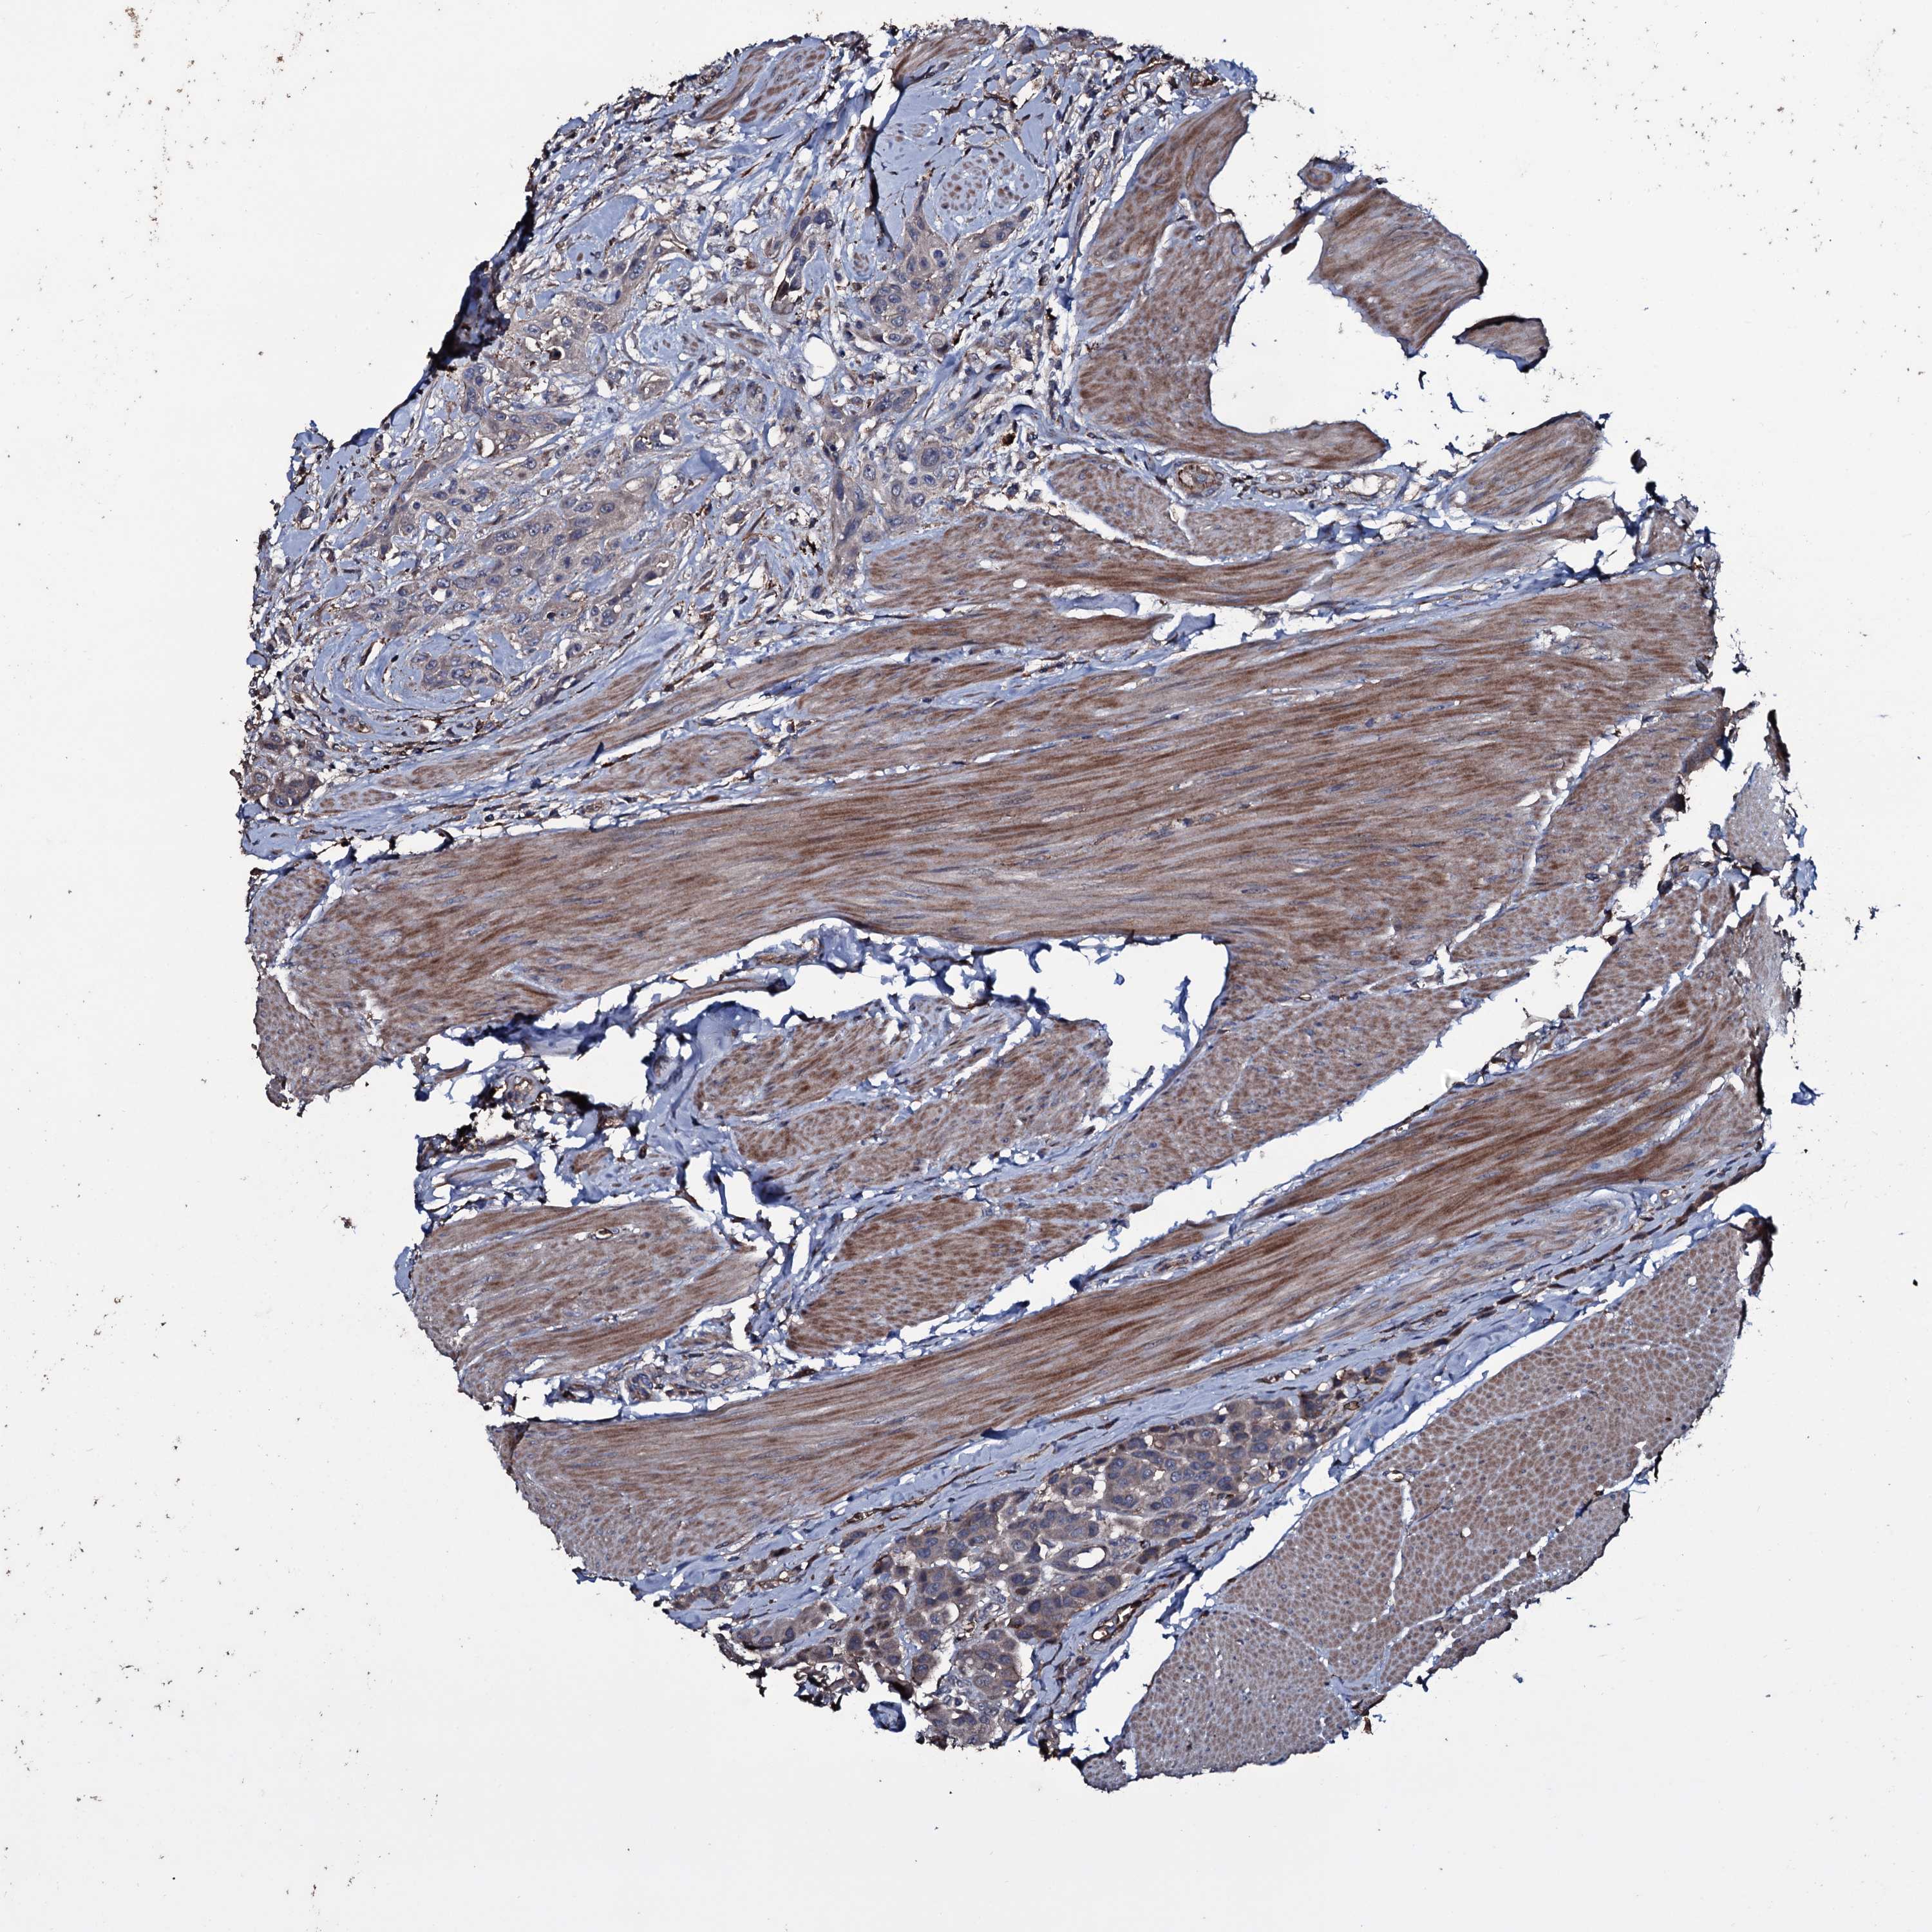

UROTHELIAL CANCER - Protein expressioni

A mouse-over function shows sample information and annotation data. Click on an image to view it in a full screen mode. Samples can be filtered based on level of antibody staining by selecting one or several of the following categories: high, medium, low and not detected. The assay and annotation is described here.

Note that samples used for immunohistochemistry by the Human Protein Atlas do not correspond to samples in the TCGA dataset.

Antibody stainingi

Antibody staining in the annotated cell types in the current human tissue is reported as not detected, low, medium, or high, based on conventional immunohistochemistry profiling in selected tissues. This score is based on the combination of the staining intensity and fraction of stained cells.

Each image is clickable and will lead to virtual microscopy that enables deeper exploration of all samples and also displays staining intensity scores, fraction scores and subcellular localization as well as patient and tissue information for each sample.

Antibody HPA041244

Staining

High

Medium

Low

Not detected

Intensity

Strong

Moderate

Weak

Negative

Quantity

>75%

75%-25%

<25%

None

Location

Nuclear

Cytoplasmic/membranous

Cytoplasmic/membranous,nuclear

Urothelial carcinoma, High grade

Urothelial carcinoma, Low grade